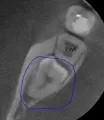

На протяжении трёх дней беспокоила несильная ноющая боль с правой стороны внизу. Сделали снимок, врач предположил, что боль возникает из-за зуба мудрости, который ещё не прорезался. И сразу записала на удаление.

Не знаю, можно ли что-то понять по приложенному снимку, но сколько примерно занимает удаление такого зуба и обязательно ли это?

Однозначно, причина беспокойств — это неправильно расположенная восьмёрка. Удаление необходимо, в противном случае мы получим скученность всего зубного ряда и потеряем седьмой зуб. Удаление сложное и требует профессионализма и опыта. Потребуется моя помощь — запишитесь к нам на приём к челюстно-лицевому хирургу.